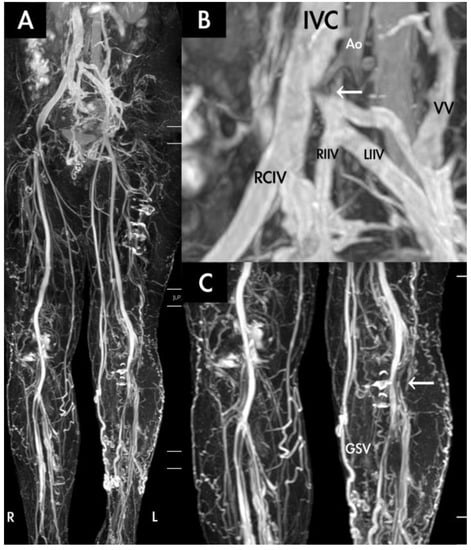

- Hsu, Y.C.; Huang, Y.K.; Hsu, L.S.; Chen, P.Y.; Chen, C.W. Using non-contrast-enhanced magnetic resonance venography for the evaluation of May-Thurner syndrome in patients with renal insufficiency: A case report. Medicine 2019, 98, e18427. [Google Scholar] [CrossRef]

- Huang, Y.K.; Tseng, Y.H.; Lin, C.H.; Tsai, Y.H.; Hsu, Y.C.; Wang, S.C.; Chen, C.W. Evaluation of venous pathology of the lower extremities with triggered angiography non-contrast-enhanced magnetic resonance imaging. BMC Med. Imaging 2019, 19, 96. [Google Scholar] [CrossRef]